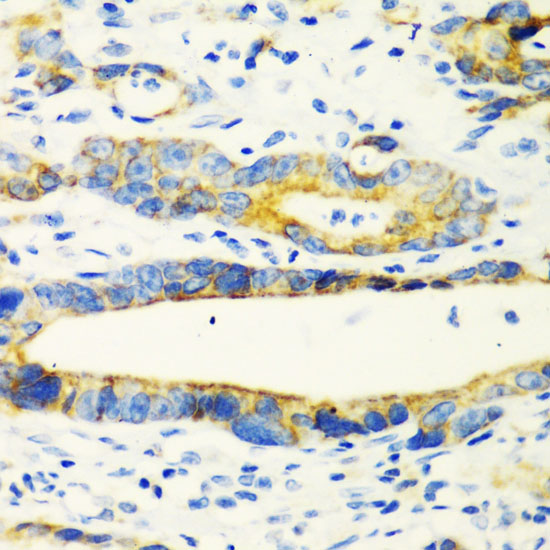

Immunohistochemistry of paraffin-embedded human esophageal cancer using CHIA at dilution of 1:100 (40x lens).

Immunohistochemistry of paraffin-embedded human gastric cancer using CHIA at dilution of 1:100 (40x lens).